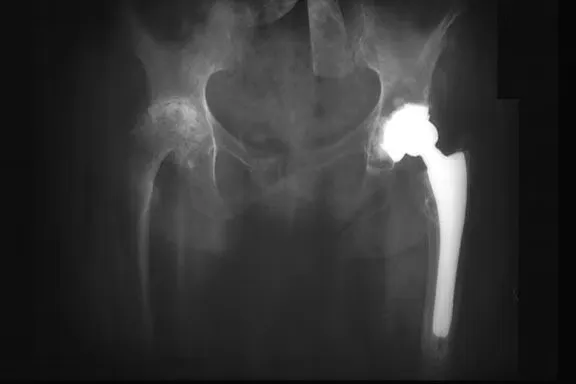

Arthroplasty is performed if all other modalities are ineffective and osteotomy is not appropriate or if a patient cannot perform ADLs despite maximal therapy. This procedure alleviates pain and may improve function. At a minimum, 10-15 years of viability are expected from joint replacement in the absence of complications.